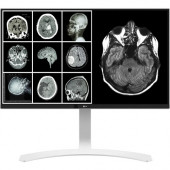

LG 27HJ712C-W - LED monitor - 4K - 8MP - color - 27..

LG 27HJ712C-W 27" LED LCD Monitor - 16:9 - 14 ms - TAA Compliant - 3840 x 2160 - 350 Nit - 1,000:1 -..